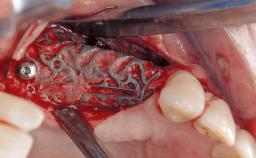

Late Presentation of Peri-Implant Mucositis Requiring Soft-Tissue Augmentation and Esthetic Crown Lengthening at Implant Site 11